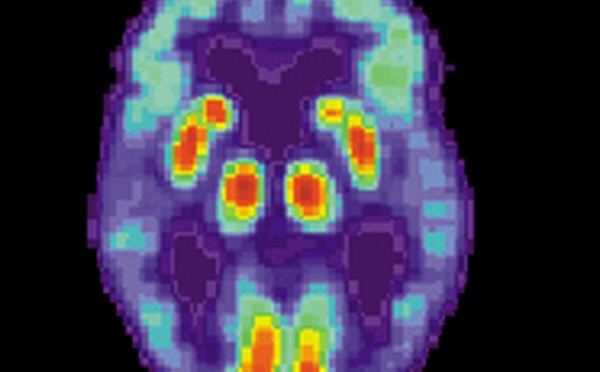

Vinculan la carencia de una hormona con el deterioro cognitivo - 07/05/2013

Investigadores de la UNED han comprobado que bajos niveles de la hormona cortisol al levantarse por la mañana se dan más en personas con problemas leves de cognición (como la fase previa al Alzhéimer y otros tipos de demencia). Los investigadores midieron el cortisol porque está relacionado con el aprendizaje y la memoria. Lo hicieron en tres momentos del día para distintas personas.